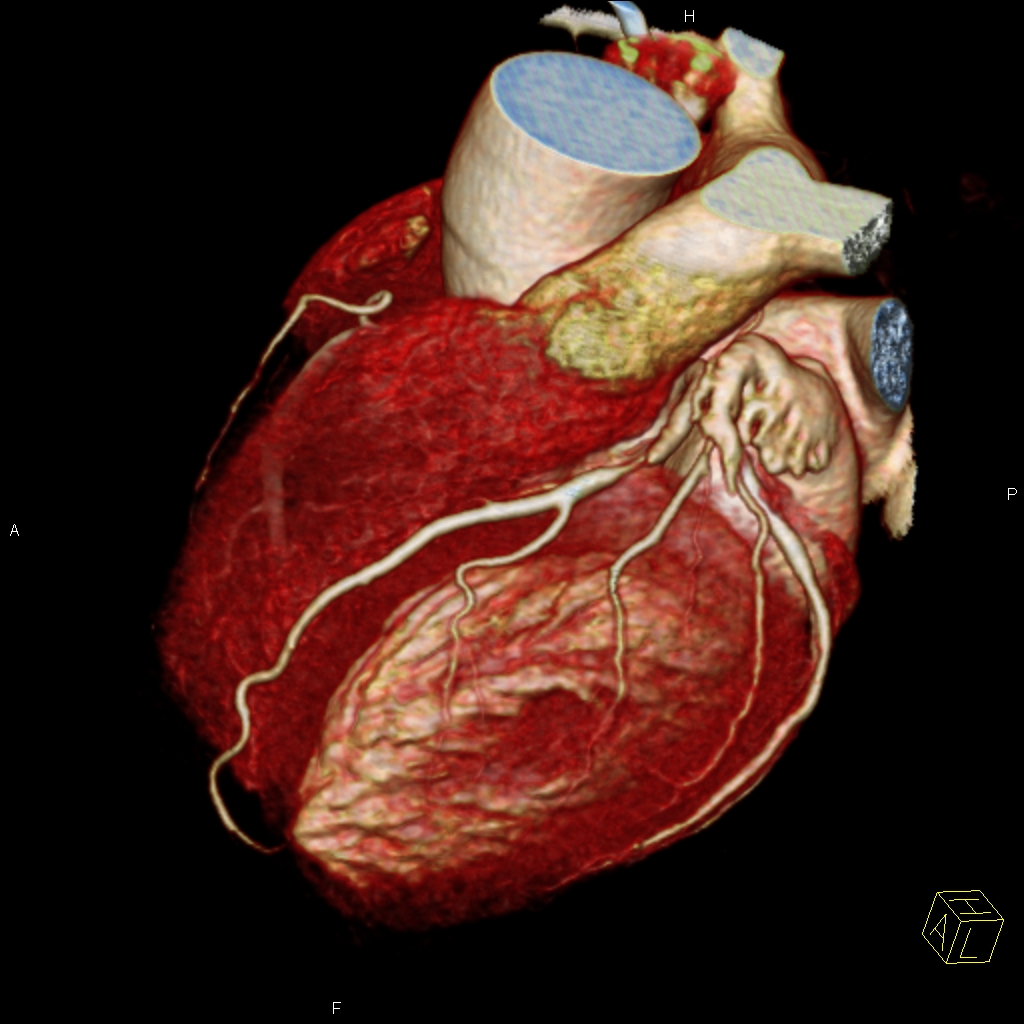

Sie hat sich als eine bedeutende Methode zur nichtinvasiven, das heisst unblutigen Darstellung der Herzkranzgefäße etabliert. Mit Hilfe der CT können bei angemessen ausgewählten und vorbereiteten Patienten mit grosser Zuverlässigkeit Aussagen über das Vorhandensein möglicher Engstellen oder Verschlüsse der Herzkranzgefässe (Abbildung 1), das Ausmass der Herzkranzgefässverkalkungen und die Anatomie des Herzens getroffen werden, und das ohne Herzkatheteruntersuchung. Sind die Herzkranzgefässe bereits erkrankt, so kann unter bestimmten Bedingungen auch eine Darstellung von Bypassgefässen (Abbildung 2) oder Stents erfolgen. Eine blutige Untersuchung mittels Herzkatheter kann somit in vielen Fällen vermieden werden (Abbildung 3). Sollten in der CT relevante Engstellen in einem oder mehreren Koronargefäßen auffallen, muss jedoch meist eine Herzkatheteruntersuchung zur weiterführenden Diagnostik und ggf. Therapie erfolgen.

Abbildung 1: CT – Schnittbild (rechts) sowie dreidimensionale Rekonstruktion (links) zeigen eine hochgradige Engstelle im Bereich der linken Herzkranzarterie.